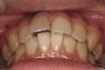

前歯の歯並びが悪いのが一番気になります。

右側では良く噛めません↓(16歳/女性)

概要・担当医コメント:叢生・右側咀嚼障害↑

マルチブラケット装置/動的治療期間26ヶ月(23回)

/費用概算:60万円

高校の部活も矯正も両方頑張れたそうです。

上顎右側の小臼歯を1本のみ抜歯させていただき,あとは上下の歯列アーチ形態の修正にて矯正できました。